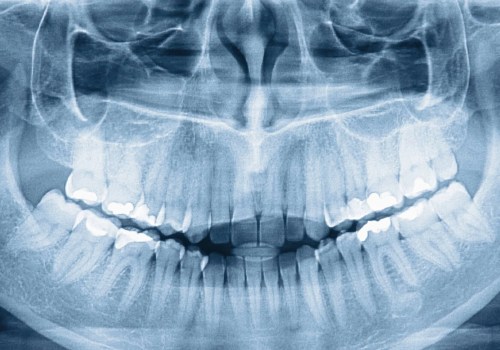

What is the difference between panoramic x-rays and full mouth x-rays?

Panoramic films A panoramic x-ray is one that surrounds the mouth from one side to the other and shows the entire...

What does a full mouth x-ray show?

Panoramic x-rays show the entire area of the mouth and all the teeth of the upper and lower jaw on a single x-ray. This...

What is a full mouth x-ray called?

Panoramic x-rays show the entire area of the mouth, all the teeth of the upper and lower jaw on a single x-ray. This...